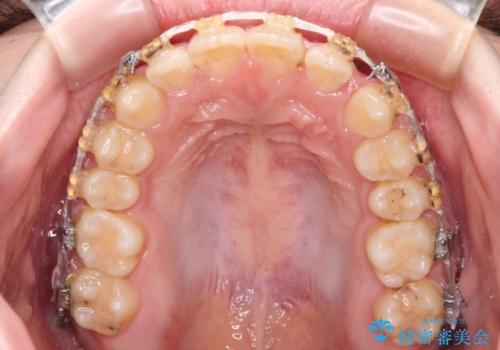

- 矯正装置

- 審美装置

- 大学病院にて装置を装着したものの、治療が十分に受けることができないとのことで転院をされた患者様です。

上顎歯列が前方にあり、口元が閉じにくくなっていたため、既に装着されている装置を使用して上顎歯列全体を後方に移動させていくこととしました。